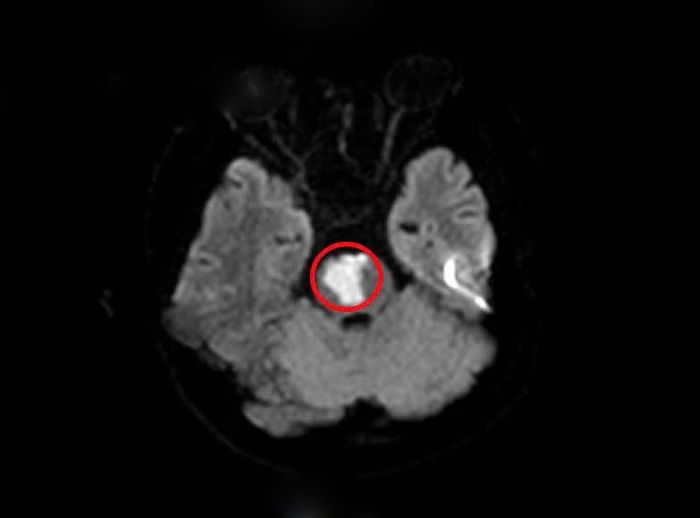

Sau khi khai thác tiền sử, các bác sĩ nghĩ nhiều đến tình trạng đột quỵ não và cho chỉ định chụp MRI sọ não. Kết quả cho thấy người bệnh có khối nhồi máu tiểu não, cầu não do tắc động mạch thân nền.

Kết quả chụp MRI.